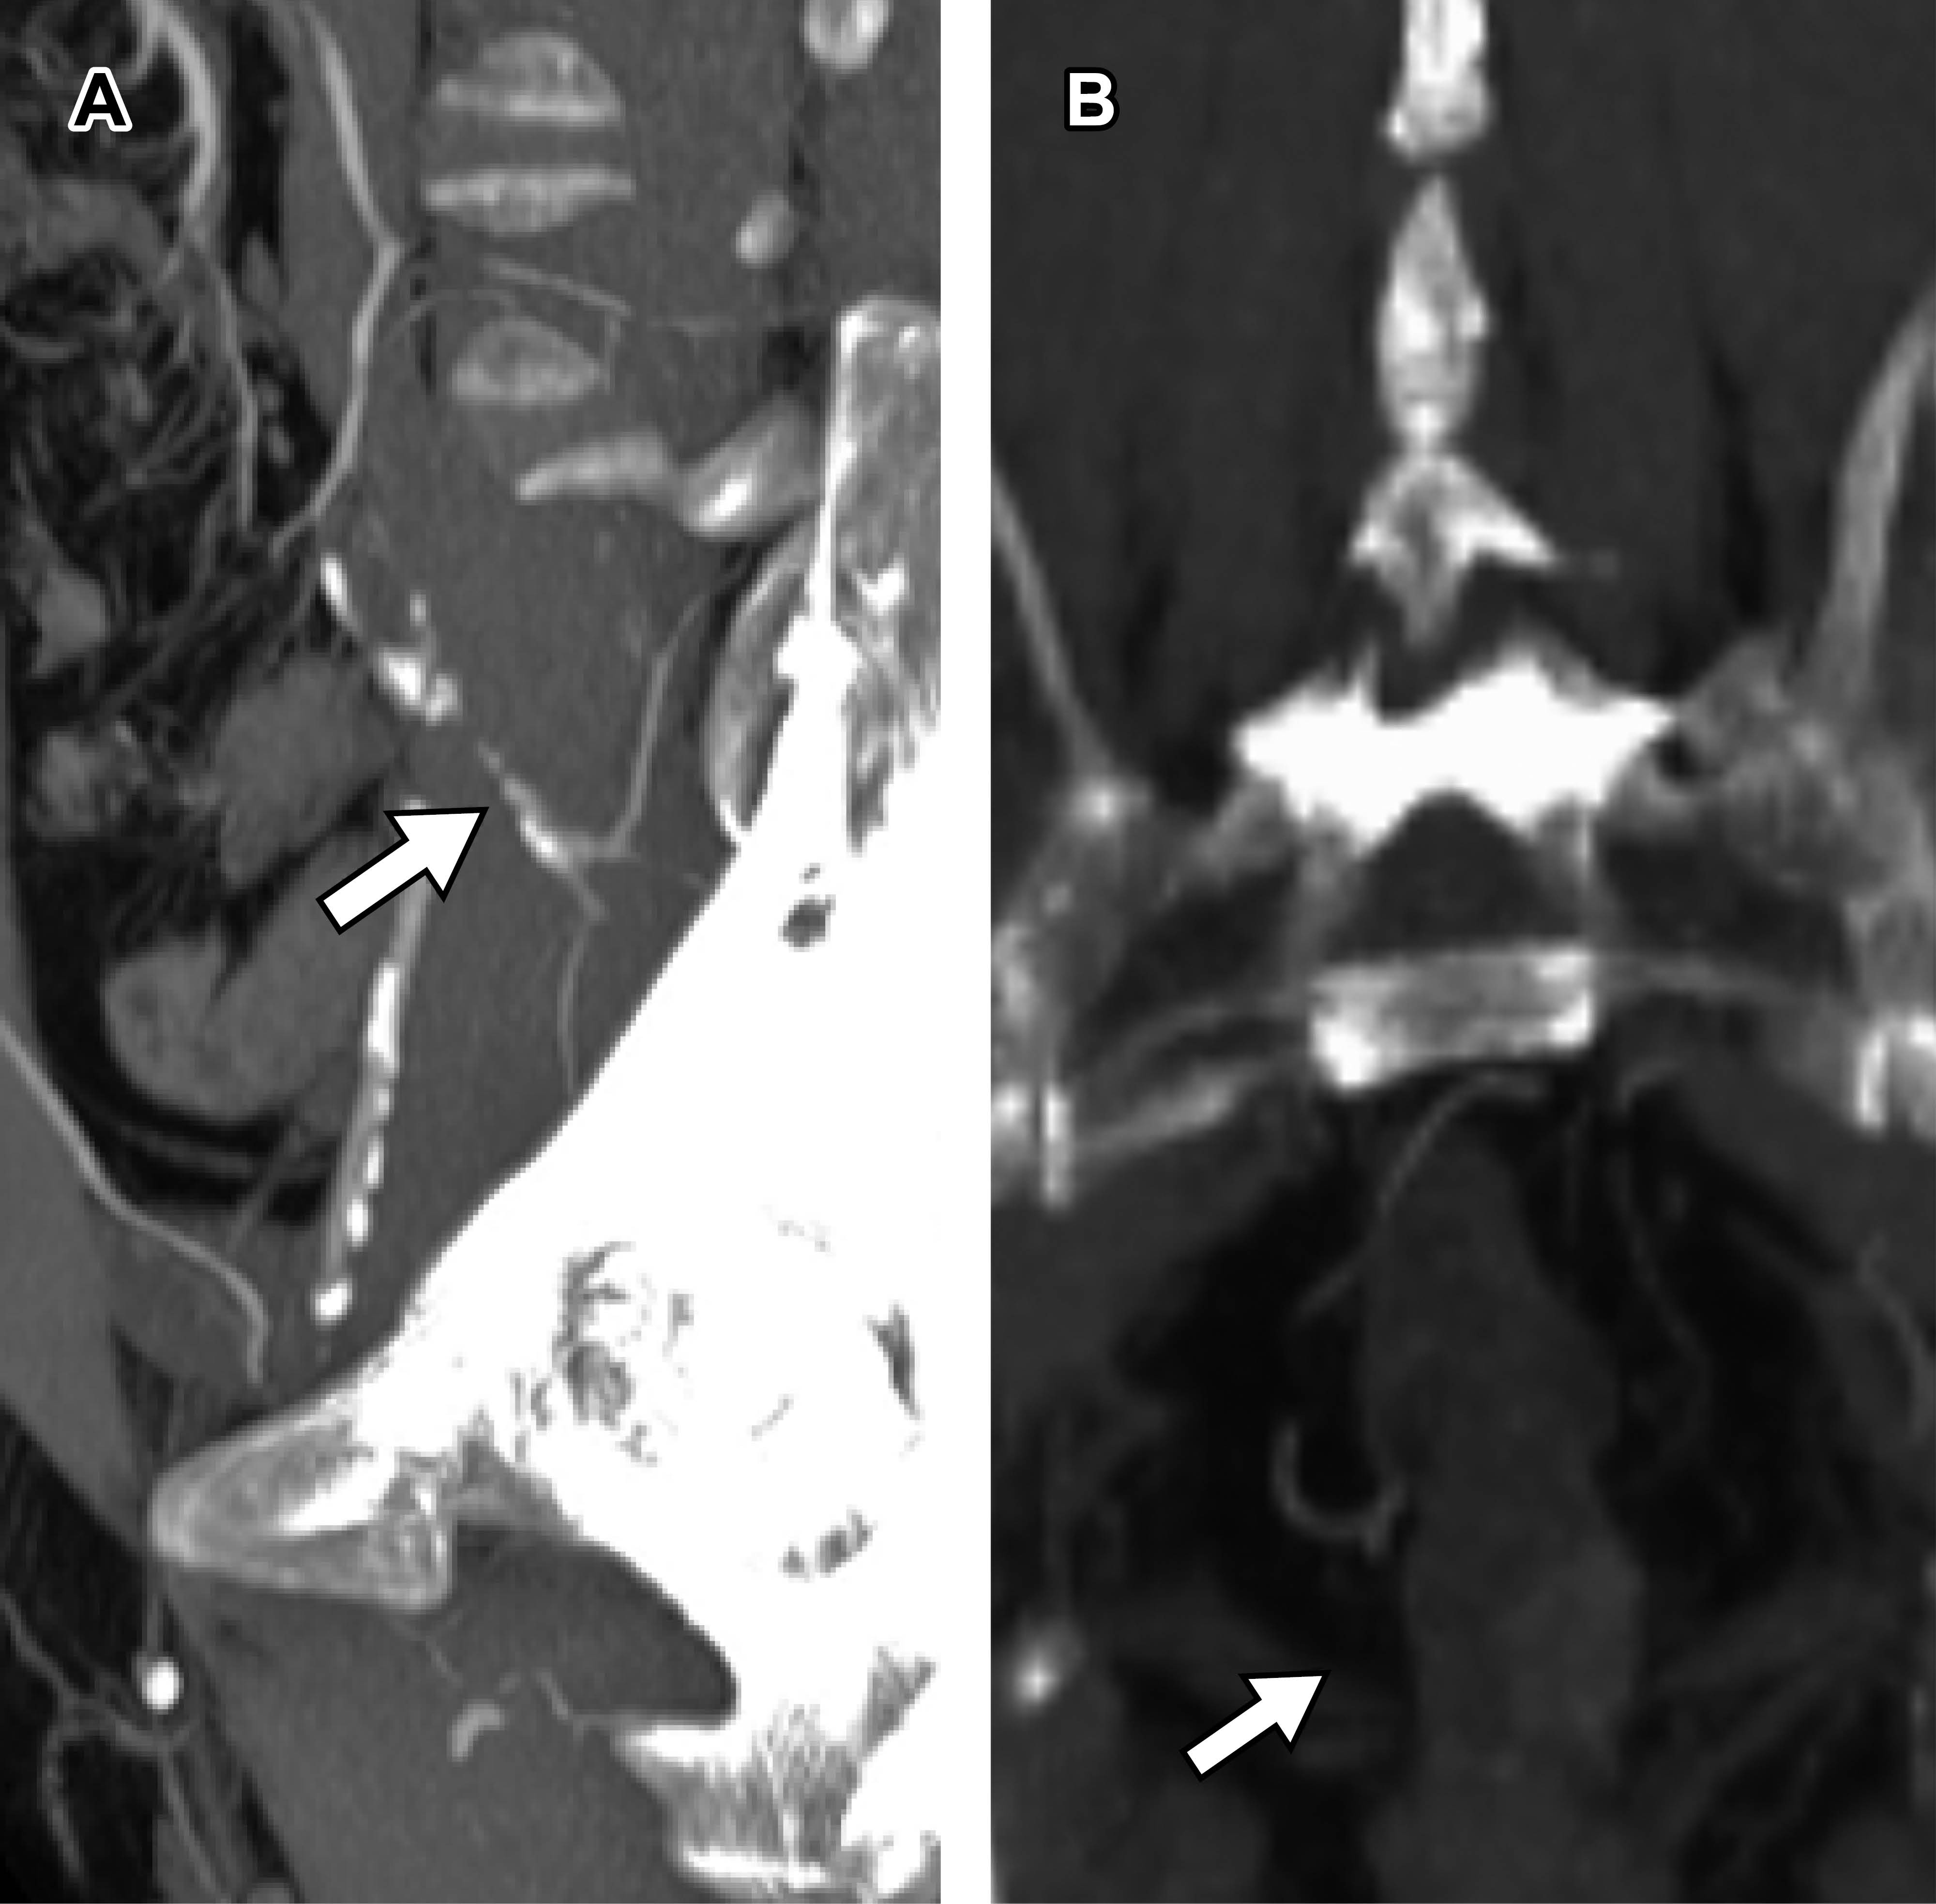

Mediante abordaje retroperitoneal se realizó bypass aortobifemoral con injerto protésico y bypass femoropoplíteo derecho con injerto protésico. Pinzamiento aórtico infrarrenal de 30 minutos, manteniendo tensión arterial media entre 80 y 90 mmHg. Al término de la cirugía, se evidenció isquemia arterial aguda en miembro pélvico izquierdo, por lo que se realizó trombectomía proximal y distal, así como bypass femoropoplíteo izquierdo con injerto protésico. Se recuperó flujo y, posteriormente, se corroboró paso de contraste con angiografía transoperatoria y TAC (Figura 2A y B). A las tres horas, posterior al procedimiento, las extremidades inferiores se encontraron eutérmicas y con adecuada coloración. Miembro pélvico derecho con pulso femoral G2, pulso poplíteo G1, no se palpó pulso tibial posterior ni pulso pedio; miembro pélvico izquierdo con pulso femoral G2, pulso poplíteo G1, no se palpó pulso tibial posterior ni pulso pedio; sin embargo, se evidenció flujo distal mediante Doppler lineal. En todo el periodo postquirúrgico, el paciente se encontró con tensión arterial media entre 80 y 90 mmHg.

A las seis horas postquirúrgicas, al terminar el efecto de la anestesia, se evidenció disminución de la movilidad y sensibilidad en las extremidades inferiores hasta un deterioro progresivo con pérdida de sensación de tacto, sensación de temperatura, dolor y propiocepción desde región genital e inferior a cresta iliaca hasta pie, por lo que se sospechó isquemia medular. Se solicitó angiorresonancia, la cual mostró cambio de intensidad de señal intrasustancia de médula, sugestivo de isquemia raquimedular. El diagnóstico fue confirmado por neurocirugía (Figura 2C y D); finalmente, se decidió manejo conservador con esteroides.

Figura 2